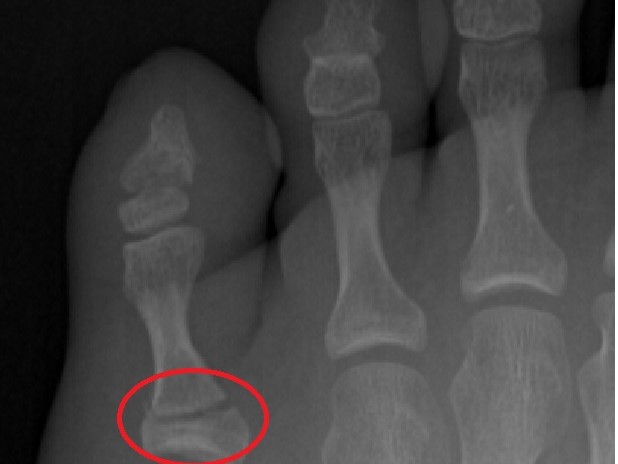

BrokeToe